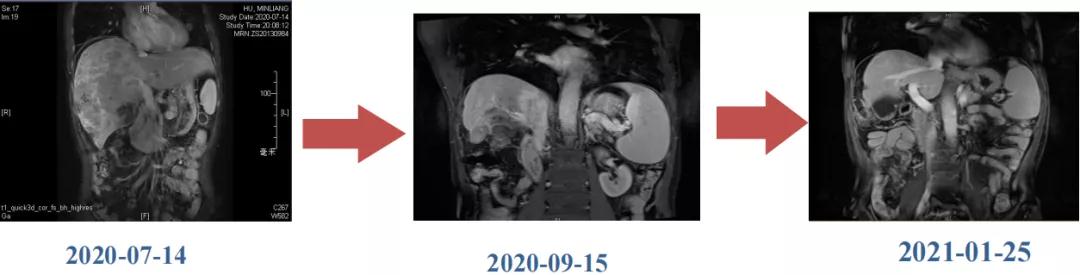

肝脏弹性超声:12kPa。腹部MRI平扫+增强:肝巨块结节性HCC(最大径18.4cm)伴肝内多发转移(最大径3.5cm),肝右静脉广泛癌栓形成;肝硬化伴门脉高压、脾大、少量腹水;肝囊肿;双肺多发转移。胸部CT平扫:两肺多发转移,两肺气肿伴肺大泡,两肺散在慢性炎症,右侧少量胸水。

Δ肝脏MRI,最大肿瘤18.4cm

肿瘤学评估(用药后2个月对比6个月):肝内主瘤明显缩小,动脉期强化降低;子灶消失;门脉右支癌栓明显缩小坏死;肺转移灶缩小,大部分消失。

Δ治疗过程中病灶影像学变化